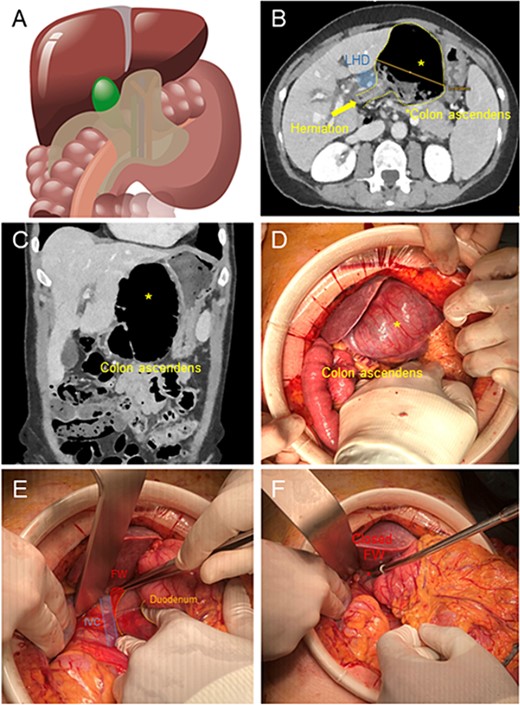

A 68-year-old woman presented in the emergency department of our hospital with epigastric pain irradiated to the back without vomiting or fever. Past clinical history included Hashimoto Thyroiditis and Polycitaemia Vera, with no previous surgical operations. The clinical examination showed a soft abdomen but with bloating, defence reaction and abdominal pain in epigastrium. Blood testing revealed 9.96 G/L leucocytes and 1 mg/l C-reactive protein. We performed a computer tomography (CT) of the abdomen, which identified a retrogastric volvulated cecum (Fig. 1B and C) and the indication to surgery was given.

(A) Illustration of cecal herniation through WF as shown in CT scan. (B) Dilated colon ascendens behind the Ligamentum Hepatoduodenale (LHD) in the CT Scan. (C) The coronary view shows the dilated colon. (D) Intraoperative hernia presentation after laparotomy, the dilated colon presents a serosal tear (*) in its surface. (E) After reduction of hernia, exposure of WF, with inferior vena cava below and Duodenum to the right. (F) Closure of WF with interrupted suture with p-Dioxanon (PDS 4-0).

We performed a 12-cm laparotomy, which allowed us to confirm the diagnosis (Fig. 1D). We incised the thin lesser sac, performed a manual derotation of the cecum and cautiously successfully pulled laterally the herniated viscera through the WF (Fig. 1E). The cecum appeared massively dilated with serosal tears. The whole ascending colon appeared lax and hypermobile. Therefore we performed a right hemicolectomy with a stapled side-to-side ileo-colic anastomosis and mesenterial closure. To prevent the recurrence of visceral herniation through the WF, we applied two simple stitches in PDS 4.0 in the inferior portion of the WF aiming to restore its normal diameter (Fig. 1F).